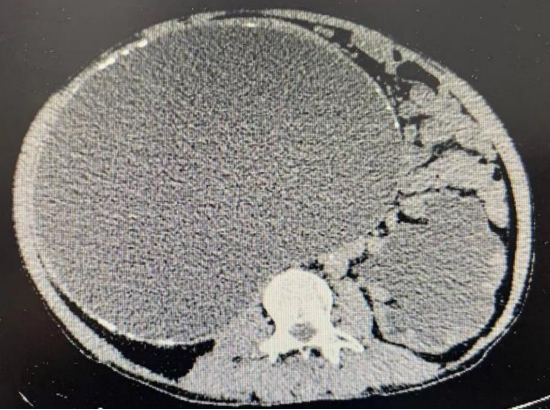

肾积水

排泄期增强ct显示右肾重度积水,肾内肾盂,右肾旋转不良.